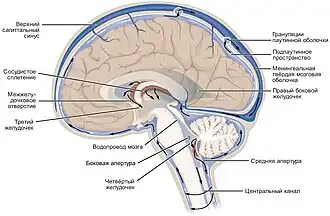

Спинномозгова́я жи́дкость, или ли́квор (лат. liquor cerebrospinalis[1]) — жидкость, постоянно циркулирующая в желудочках головного мозга, ликворопроводящих путях, субарахноидальном (подпаутинном) пространстве головного и спинного мозга[2].

Циркуляция

Ликвор образуется в мозге: в эпендимальных клетках сосудистого сплетения (50—70 %), вокруг кровеносных сосудов и вдоль желудочковой стенки. Далее цереброспинальная жидкость циркулирует от боковых желудочков в отверстие Монро (межжелудочковое отверстие), затем — вдоль третьего желудочка, проходит через Сильвиев водопровод. Затем проходит в четвёртый желудочек, через отверстия Мажанди и Лушки выходит в субарахноидальное пространство головного и спинного мозга. Ликвор реабсорбируется в кровь венозных синусов и через грануляции паутинной оболочки.